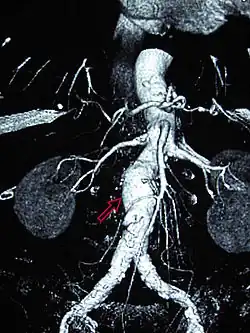

Aortic aneurysms are classified by their location on the aorta.

- An aortic root aneurysm, or aneurysm of the sinus of Valsalva.

- Thoracic aortic aneurysms are found within the chest; these are further classified as ascending, aortic arch, or descending aneurysms.

- Abdominal aortic aneurysms, "AAA" or "Triple A", the most common form of aortic aneurysm, involve that segment of the aorta within the abdominal cavity. Thoracoabdominal aortic aneurysms involve both the thoracic and abdominal aorta.

- Thoracoabdominal aortic aneurysms comprise some or all of the aorta in both the chest and abdomen, and have components of both thoracic and abdominal aortic aneurysms.[8] The Crawford classification describes five types.[9]

Endovascular treatment of aortic aneurysms is a minimally invasive alternative to open surgical repair. It involves the placement of an endovascular stent through small incisions at the top of each leg into the aorta.